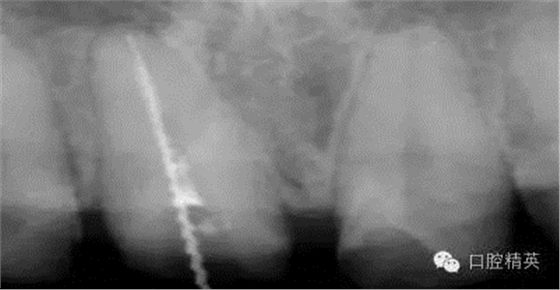

根管治療更是牙體修復(fù)的基礎(chǔ),根據(jù)術(shù)前診斷,對(duì)需要做根管治療的或有必要重新做根管治療的,一定要做到恰充,消除隱患,避免將來冠修復(fù)好后,出現(xiàn)根尖炎癥的問題(見圖3、4、5)。在基礎(chǔ)工作做好后,接下來開始牙體預(yù)備,根據(jù)跟個(gè)人習(xí)慣,選擇合適的車針(圖6、7)。